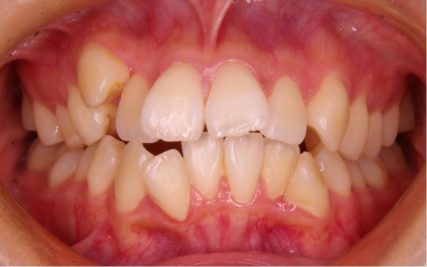

でこぼこ/20代女性

- 不正咬合/叢生(でこぼこ)

- 治療前

- 上下とも前歯のスペース不足が認められた。歯のサイズと顎の幅とのバランスが不調和な事が原因の1つとして考えられる。

- 治療後

- 前歯部のでこぼこが解消され、正常咬合を獲得する事が出来た。又、歯科矯正用アンカースクリューを用いる事で抜歯スペースを有効に利用できた。